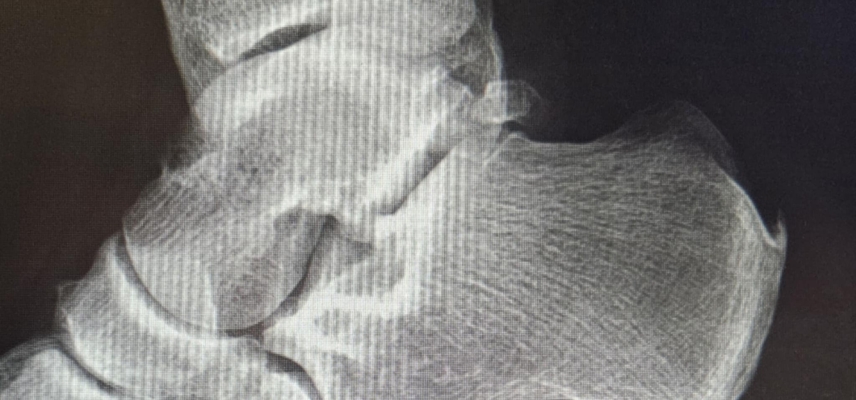

Ostroga piętowa to zwapnienie (wyrośl kostna), które pojawia się na dolnej części kości piętowej, w miejscu przyczepu rozcięgna podeszwowego. Co ciekawe, sama ostroga nie zawsze boli – może być widoczna na RTG, ale nie dawać żadnych objawów. Ból pojawia się zazwyczaj wtedy, gdy towarzyszy jej stan zapalny tkanek miękkich, czyli właśnie zapalenie rozcięgna podeszwowego.